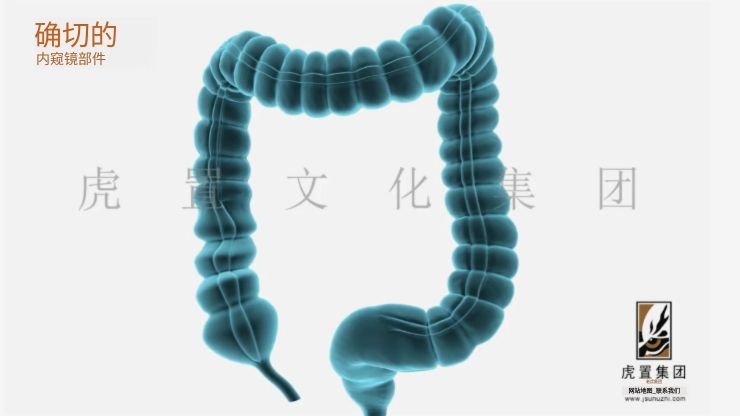

- > 医疗三维动画用到哪些技术-虎置文化集团2026-03-18

- > 医疗器械三维动画怎么收费-虎置动画2026-03-17

- > 医学手术动画有哪些优势-虎置文化集团2026-03-02

- > 医学三维动画都有哪些优势-虎置动画制作2026-02-06

- > 怎么制作医疗三维产品动画视频-虎置动画2026-01-23

- > 医疗设备动画的作用主要有哪些-虎置动画2026-01-16

- > 医学三维动画有哪些特点和优势-虎置动画2026-01-13